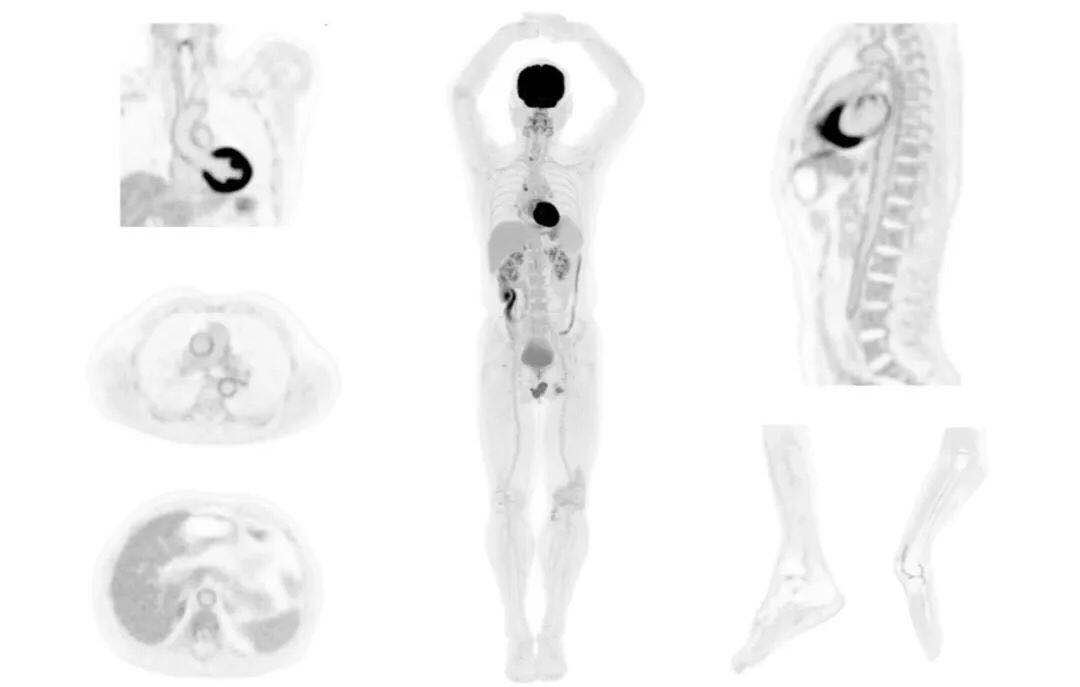

uExplorer探索者不再局限于傳統(tǒng)靜態(tài)代謝過程3D成像,而是在此基礎(chǔ)上新增一個維度——時間,從而實現(xiàn)4D全景成像。

注射總劑量為7.8mCi,14分鐘全身采集時間,在擁有超高靈敏度與超高分辨率的uEXPLORER上,即可得到展示顯示人體諸多精細結(jié)構(gòu)的高清三維圖像。